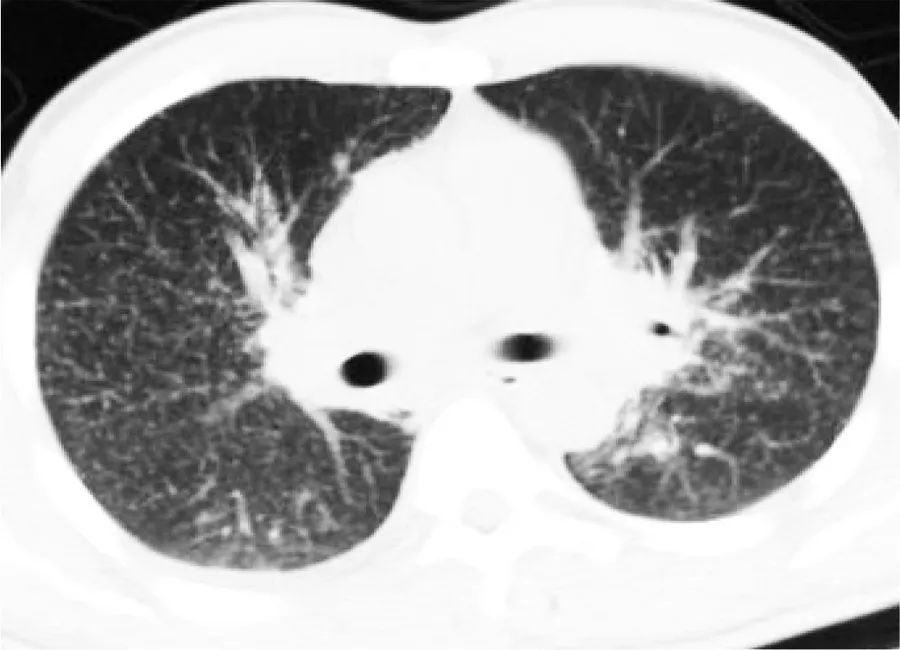

胸部CT:粟粒性肺结核